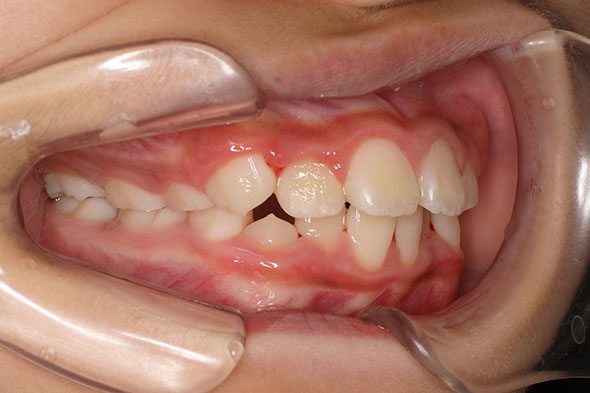

側方歯(犬歯、小臼歯)の生え変わりの時期。 前歯のがたつきを気にされ、小児矯正からの治療を希望されました。 お母様は、矯正治療経験済みですので、治療には前向きで早期治療の必要性を納得されていました。 小児矯正では、永久歯の生え変わるためのスペースを増加させ、がたつきを軽減させることを目的で行います。 残ったがたつきは、全ての永久歯が生え変わってから、本格矯正(マルチブラケット装置での治療)で改善しています。 比較的、叢生量は少ないため、本格矯正は非抜歯にて配列しました。

マルチブラケット 動的治療期間 2年6か月 調整回数16回 特に問題もなく、保定後も安定しています。